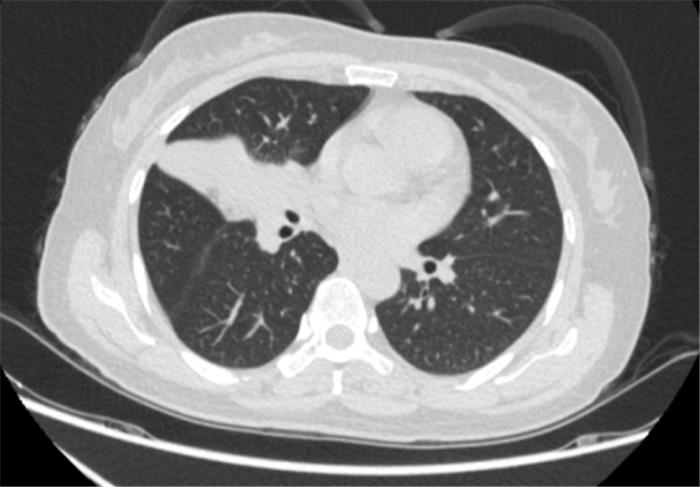

覃寿明教授团队为李女士进行了4个周期的化疗联合免疫新辅助治疗。覃寿明介绍,肿瘤的免疫治疗是通过激活人体免疫系统,依靠自身免疫机能实现杀灭肿瘤细胞和肿瘤组织。免疫治疗的作用更持久,副作用也相对更低。

经过4个周期的治疗后复查发现:李女士的病灶明显缩小,实现了降低肺癌分期。

患者治疗前基线胸部CT

免疫联合化疗新辅助治疗4周期后胸部CT